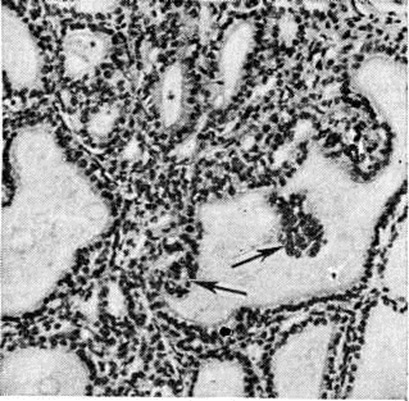

Патологическая анатомия характеризуется наличием трёх морфологический форм Зоб эндемический: разлитой (диффузной), узловой (нодозной) и смешанной (диффузно-узловой). В начале заболевания наблюдается диффузная форма с равномерным увеличением железы при неизменённых её контурах. Образование отдельных центров пролиферации приводит к развитию узловой или смешанной формы зоба. При узловой гиперплазии иногда обнаруживаются множественные узлы, различные по форме, плохо отграниченные от окружающей ткани, но сохраняющие тенденцию к росту. Микроскопически Зоб эндемический гетерогенен. Диффузный зоб представлен нормальной или микрофолликулярной тканью. В зависимости от функционального состояния фолликулы содержат базофильный, «густой» или только просвечивающий, почти прозрачный эозинофильный коллоид. В покое эпителий фолликулов кубический или плоский; в состоянии функциональной активности он становится высоким, светлым, образует сосочковидные выпячивания в полость фолликула (рисунок 1). В диффузных и узловых зобах встречаются трабекулярные и тубулярные структуры. Предполагается, что чем тяжелее эндемия зоба, тем чаще встречаются малодифференцированные формы паренхиматозного зоба (тубулярная и трабекулярная). Коллоидный зоб построен из фолликулов различной величины (макро и микрофолликулярный), богатых коллоидом, дающим положительную реакцию на РНК, белки и мукополисахариды. Комбинация фолликулов различной величины создаёт пёструю картину коллоидного зоба (рисунок 2 и 3). В зобах могут обнаруживаться инволюционные изменения (кровоизлияния, дистрофические процессы) с дальнейшим отложением в изменённых участках извести и холестерина. Паренхиматозные и коллоидные формы зоба могут трансформироваться в фиброзную форму с увеличением соединительнотканных образований. Солитарные аденомы (узлы) быстрее подвергаются различным инволюционным изменениям в связи с особым типом кровообращения. Узловой зоб может подвергаться малигнизации. Хотя нет достаточно убедительных данных о том, что Зоб эндемический чаще малигнизируется по сравнению со спорадическим, однако солитарная аденома в условиях эндемии зоба рассматривается как проблема онкологическая.